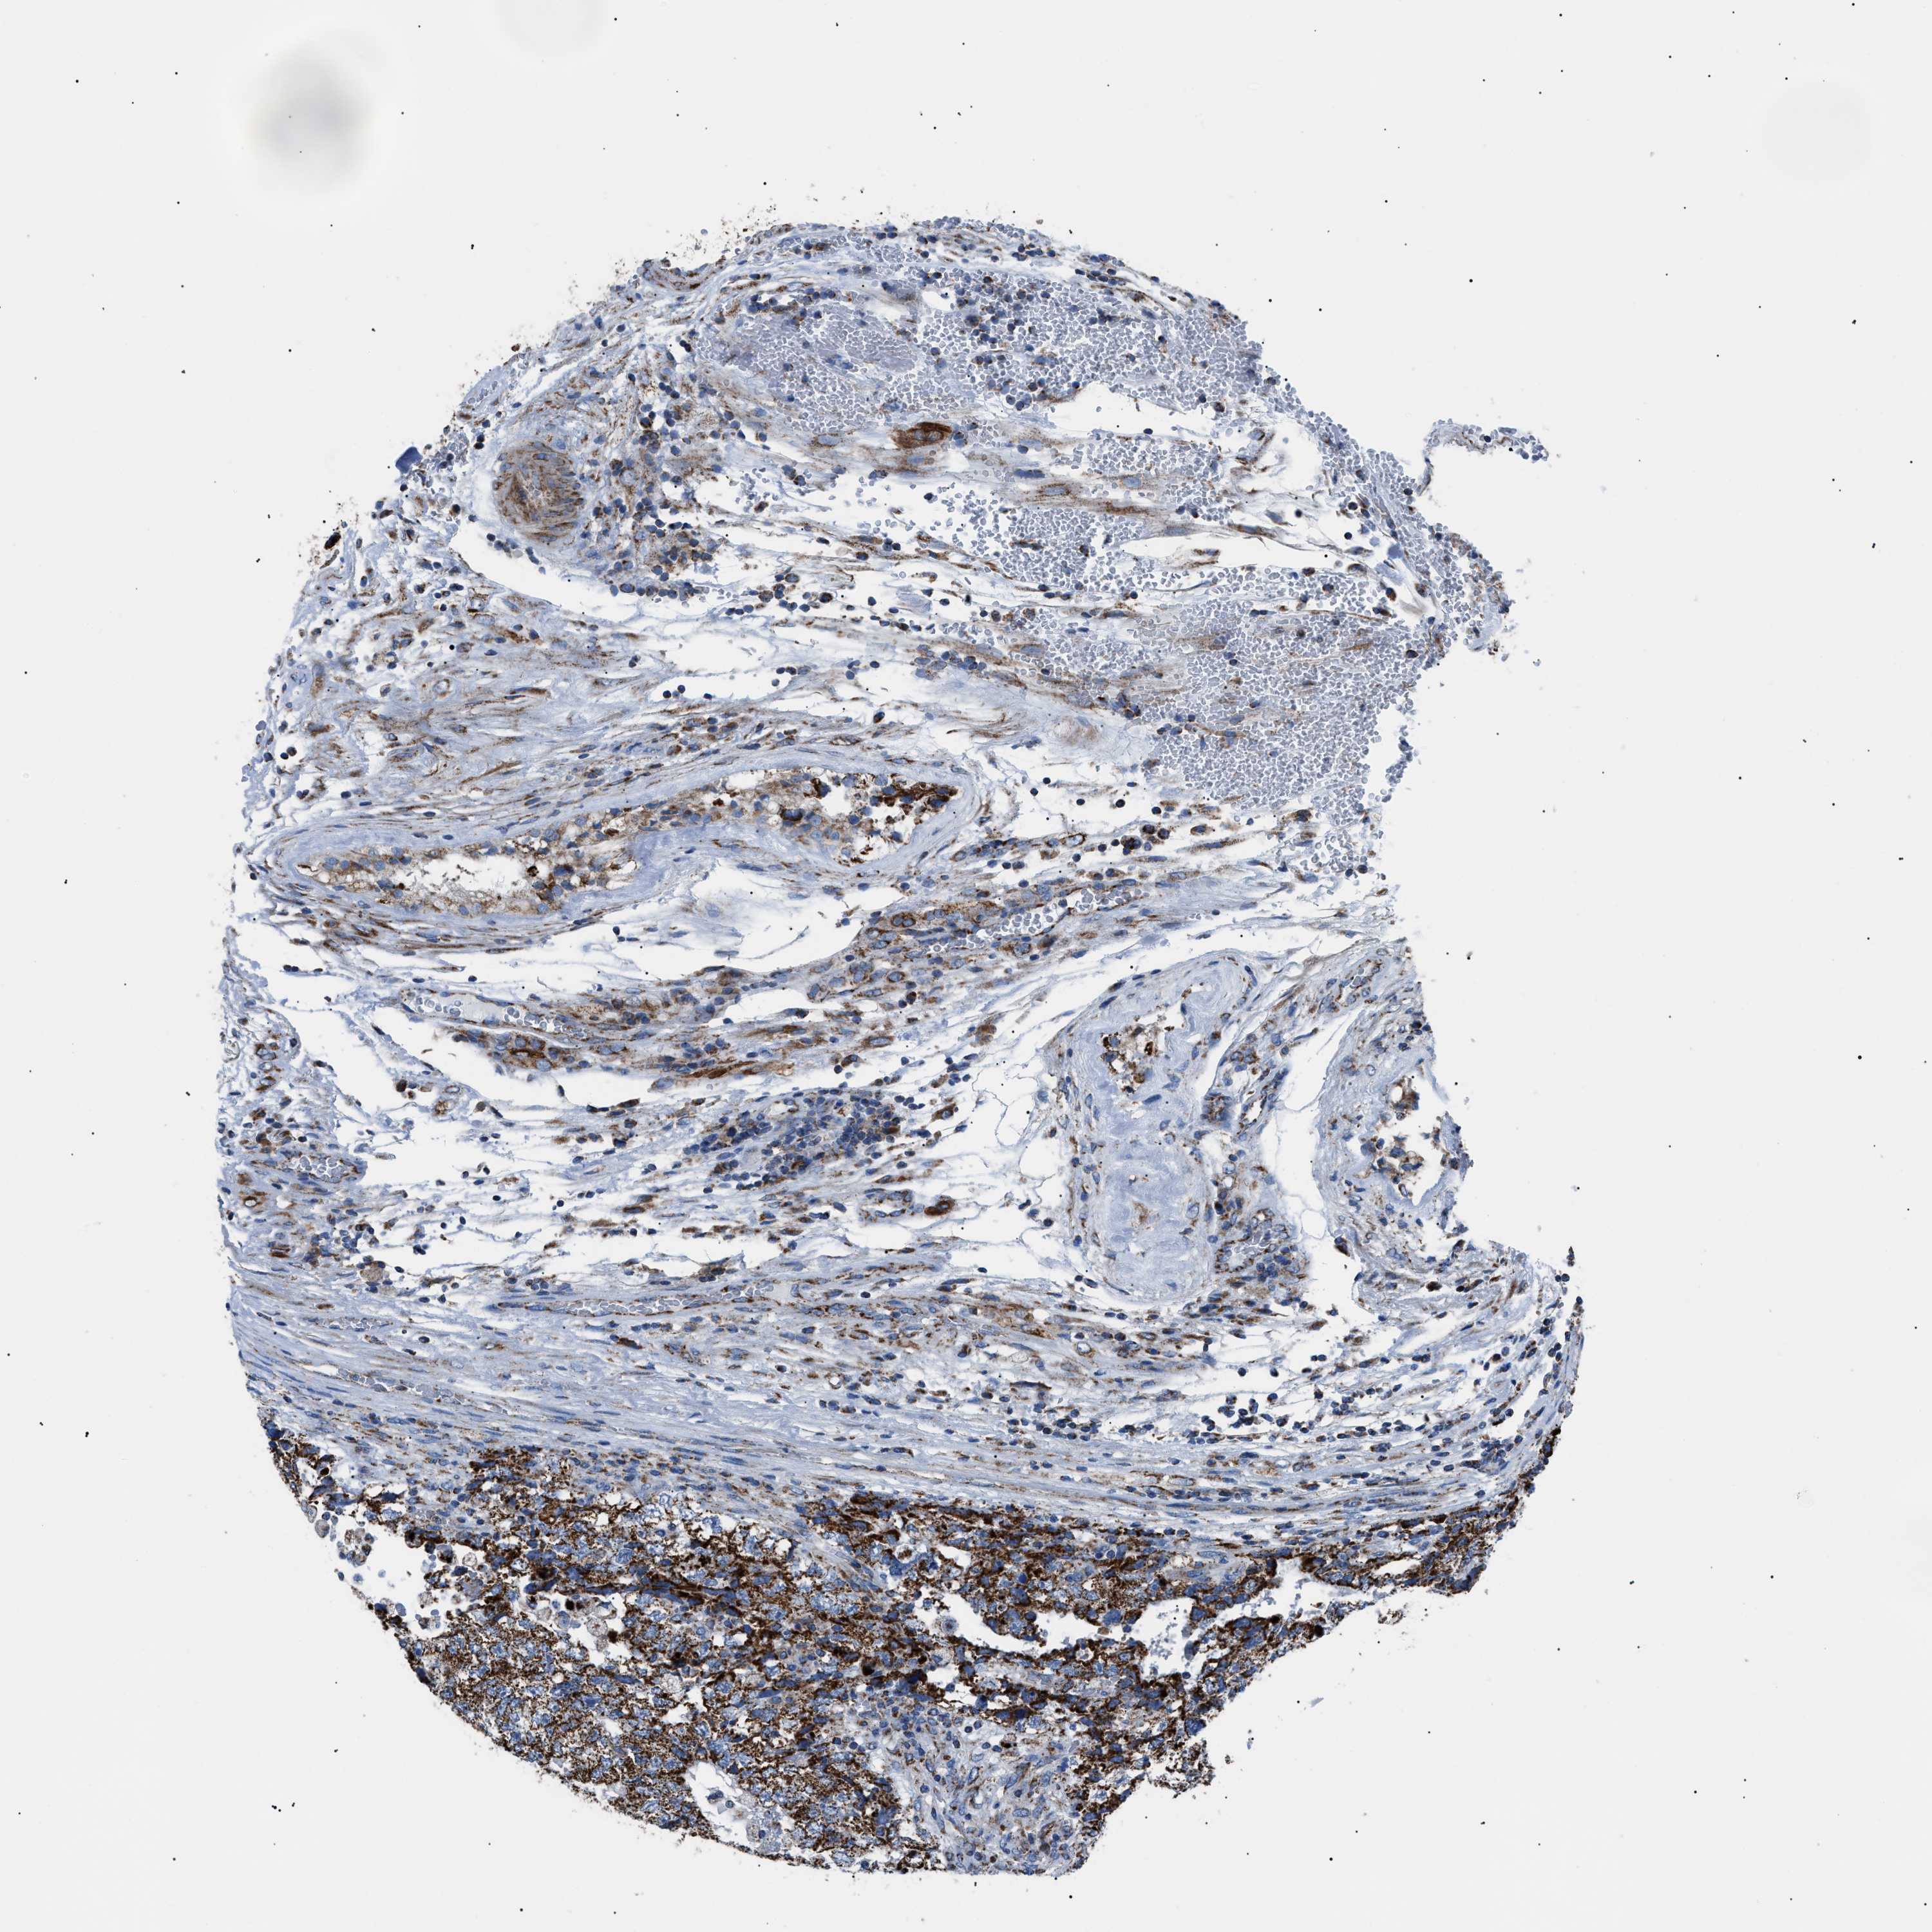

TESTIS CANCER - Protein expressioni

A mouse-over function shows sample information and annotation data. Click on an image to view it in a full screen mode. Samples can be filtered based on level of antibody staining by selecting one or several of the following categories: high, medium, low and not detected. The assay and annotation is described here.

Note that samples used for immunohistochemistry by the Human Protein Atlas do not correspond to samples in the TCGA dataset.

Antibody stainingi

Antibody staining in the annotated cell types in the current human tissue is reported as not detected, low, medium, or high, based on conventional immunohistochemistry profiling in selected tissues. This score is based on the combination of the staining intensity and fraction of stained cells.

Each image is clickable and will lead to virtual microscopy that enables deeper exploration of all samples and also displays staining intensity scores, fraction scores and subcellular localization as well as patient and tissue information for each sample.

Antibody CAB026335

Carcinoma, Embryonal, NOS

Seminoma, NOS